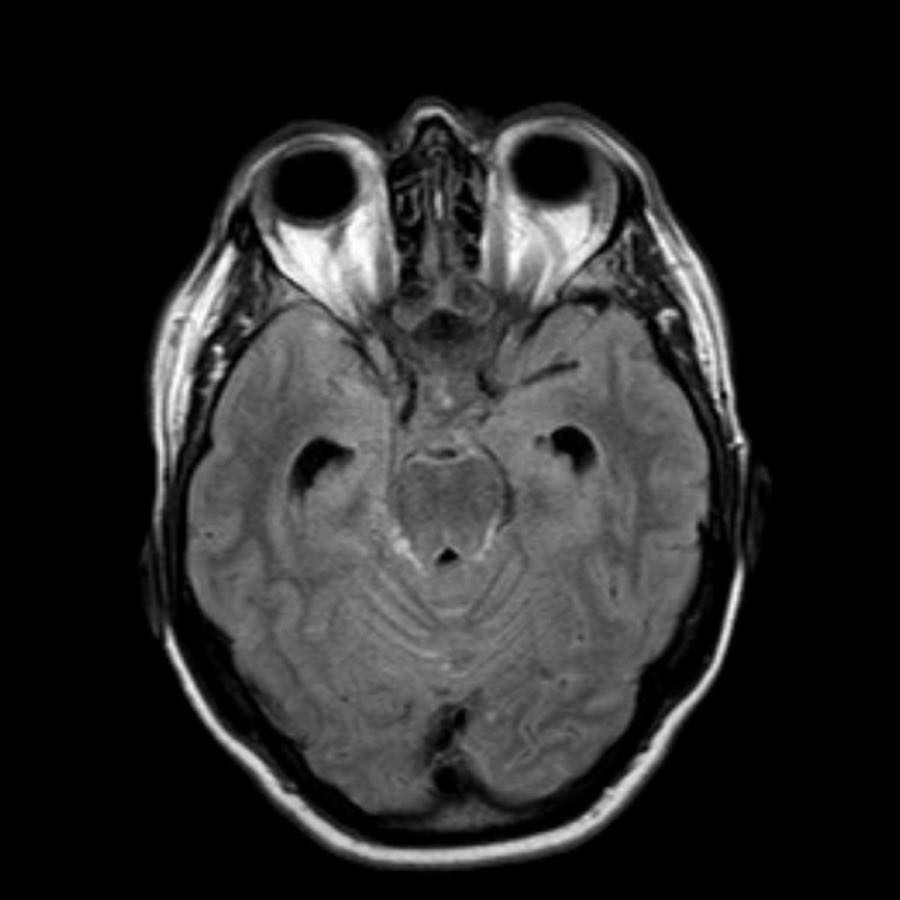

Bệnh nhân này nhập viện với xuất huyết tiểu não.

Các hình ảnh chuỗi xung gradient echo cho thấy nhiều vi xuất huyết.

Đây có thể là hậu quả của tăng huyết áp lâu năm do vị trí trung tâm của một số vi xuất huyết.